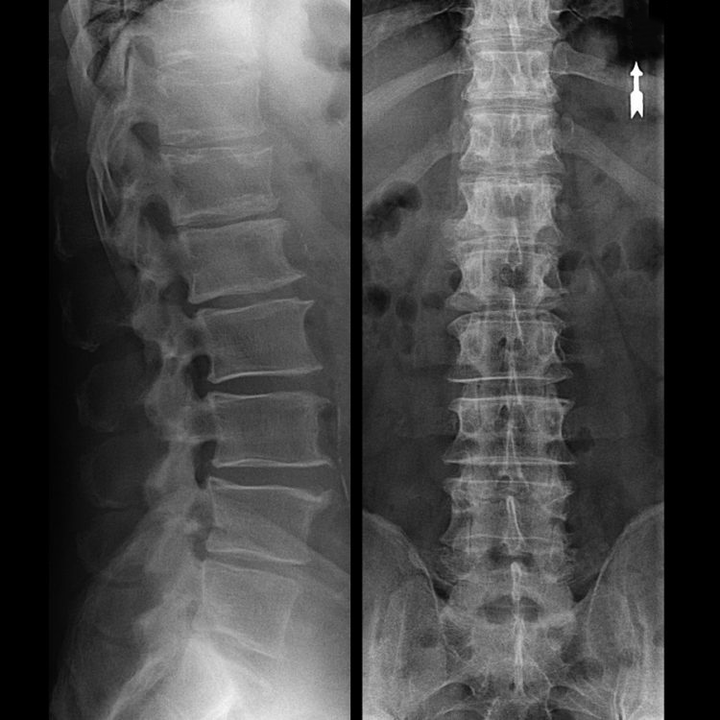

In typical cases, osteoarthritis of the cervical and cervicothoracic spine occurs as described above.Therefore, the main stage of diagnosis remains the identification of the patient's complaints, determining the presence of concomitant muscle spasms by simple palpation of the muscles along the spine.Can the diagnosis of osteoarthritis be confirmed with an X-ray?

An “X-ray” of the cervical spine and even with functional tests of flexion and extension do not show cartilage because their tissue transmits X-rays. Despite this, based on the position of the vertebrae, one can draw general conclusions about the height of the intervertebral discs, the general straightness of the physiological curvature of the neck - scoliosis, as well as the presence of marginal growths on the vertebrae with prolonged irritation of their surfaces by fragile and dehydrated intervertebral discs.Functional tests can confirm the diagnosis of cervical spine instability.

Since the disc itself can only be seen using CT or MRI, magnetic resonance imaging and X-ray computed tomography are indicated to clarify the internal structure of the cartilage and components such as protrusions and herniations.Therefore, with the help of these methods, the diagnosis will be made accurately and the results of the CT scan will be an indication, even a local guide for surgical treatment of hernia in the neurosurgery department.